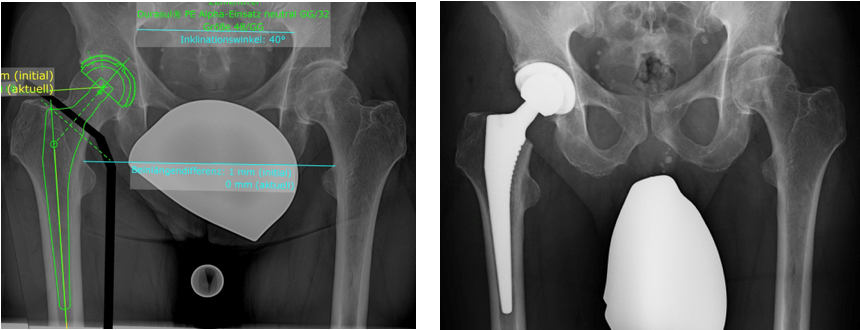

(Bilder oben: Digitale Prothesenplanung einer Hüft-TEP rechts – vor OP und postoperative Kontrolle)